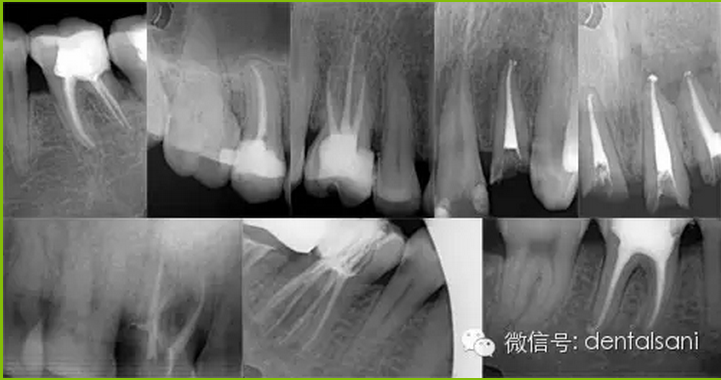

適應(yīng)癥要選擇恰當(dāng)。根據(jù)病情,牙周狀況、X線(xiàn)片,病人的身體狀況等各方面因素來(lái)選擇,避免治療失敗。

4. 開(kāi)髓時(shí)要參照X線(xiàn)片,鉆針不宜進(jìn)入髓腔太深,以免損傷和磨穿髓底。如果底損傷后,則難以尋找根管口,有條件者用根管口擴(kuò)大器。萬(wàn)一髓底磨穿,可以用丁香油氧化鋅暫封穿底處后(穿底大,應(yīng)先用雙氧水、生理鹽水輕輕沖洗),再繼續(xù)擴(kuò)管。待炎癥消除后,再用磷酸鋅或銀汞合金將底充好,根管治療應(yīng)繼續(xù)進(jìn)行。另外,凡是別人治療過(guò)的、開(kāi)過(guò)髓的牙齒,接手之后必先拍X線(xiàn)片,因?yàn)橛袝r(shí)已經(jīng)穿底。